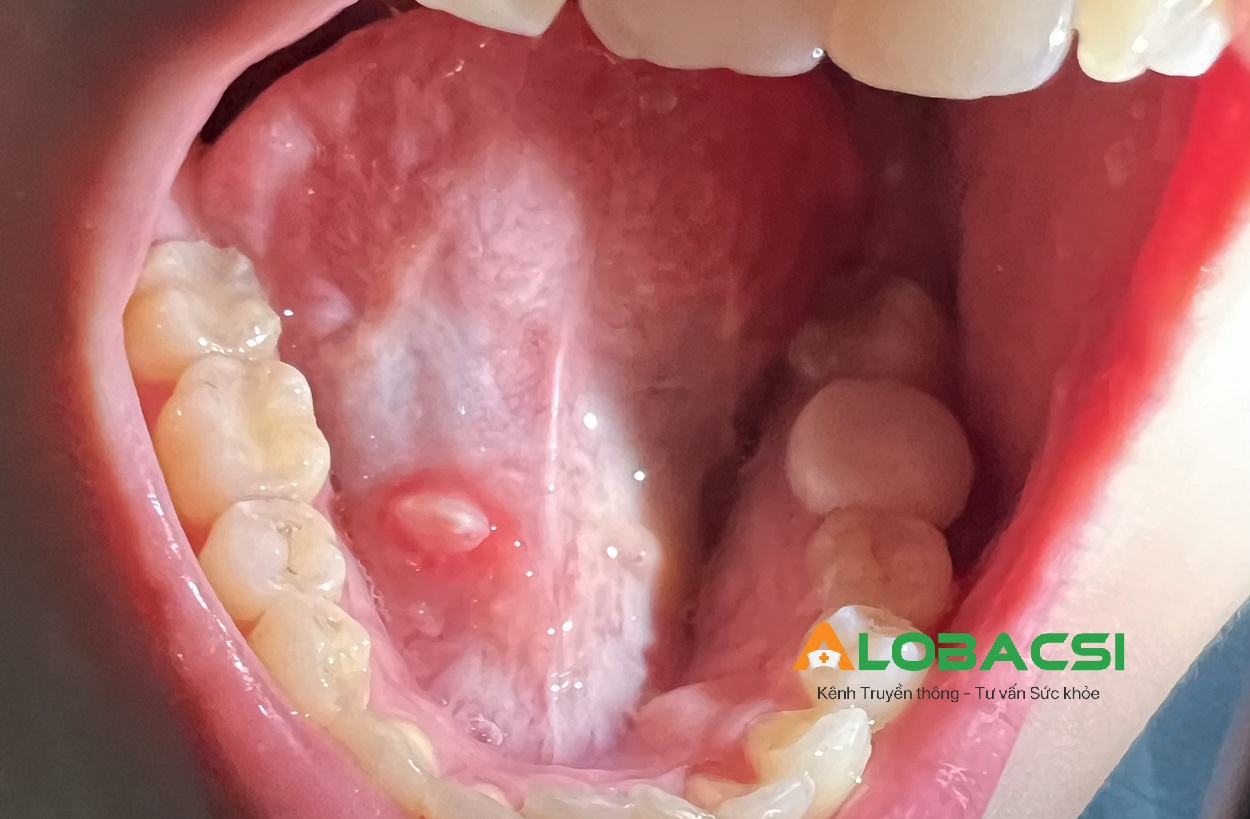

AloBacsi cho em hỏi. Dưới lưỡi em có nổi cục thịt trắng đỏ như hình ạ. Khi đánh răng gây đau rát, em không biết có phải sùi mào gà dưới lưỡi không ạ? Và nếu vậy hoặc bệnh khác thì em có thể sử dụng thuốc hoặc điều trị bằng phương pháp nào ạ? Kính mong các bác sĩ cho lời khuyên. Em cảm ơn nhiều.

Qua hình ảnh bạn gửi, tổn thương dưới lưỡi là một nốt tròn, nền đỏ, ở giữa có giả mạc trắng, gây đau rát khi chạm vào. Hình thái này phù hợp nhiều với loét áp tơ (nhiệt miệng) hơn là sùi mào gà.

Sùi mào gà ở miệng thường do HPV gây ra, tổn thương có dạng nhú gai, sần sùi như súp lơ hoặc mào gà, ít khi đau rát nhiều như bạn mô tả. Trong khi đó, loét áp-tơ thường là vết loét nông, bờ đỏ, đáy trắng vàng, rất đau khi ăn uống hoặc chạm vào - đặc biệt khi đánh răng.